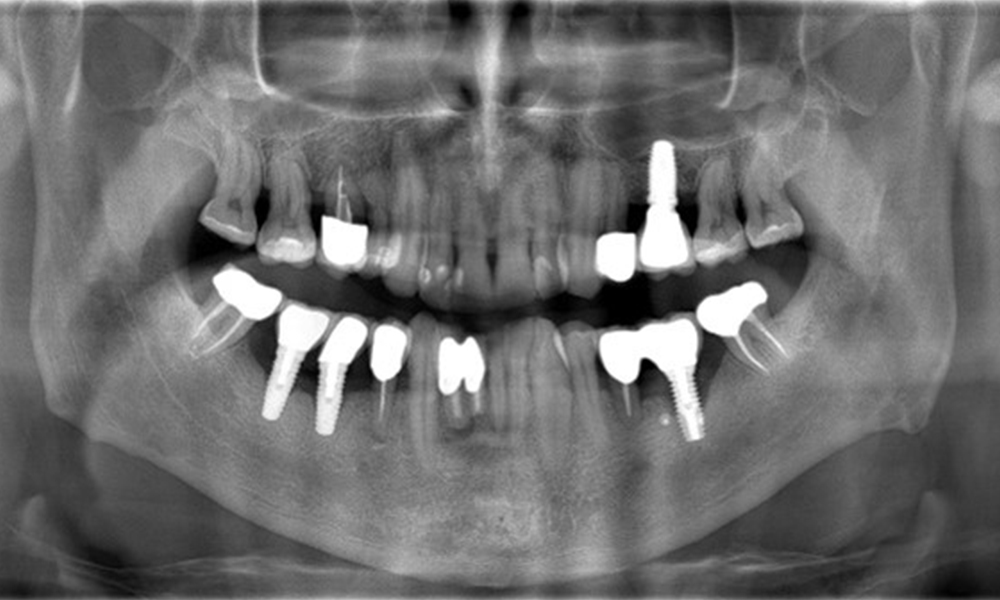

52-годишен пациент се явява на профилактичен преглед. Пациентът няма хронични заболявания и не приема никакви лекарства. Претърпял е различни дентални лечения и също така има две активни кариозни лезии. Освен това има четири импланта (2-ри, 3-ти и 4-ти квадрант). Установява се, че има ранно пародонтално заболяване (стадий IV, степен В). Състоянието на пародонта е стабилно, като дълбочина на сондиране (ST) от 5 mm се проявява само при импланта в област 36. Установен е и гингивит.

В историята на заболяването на пациента няма особени рискови фактори със специфични дентални последици. Следователно ключовият фактор е изискването по отношение на оралното здраве. В това отношение има данни за дълбочина на сондиране от 5 mm при импланта в 3-ти квадрант, а на рентгеновата снимка - за увеличена костна загуба. Пациентът също така има стабилно понастоящем пародонтално заболяване и две активни начални кариозни лезии.

Рентгеновите снимки показват прогресията на костната загуба. ОПГ от 29.06.2020 г. (вляво) и ОПГ от 26.02.2024 г. (вдясно).

ОПГ: 26/02/2024 Дентална рентгенова снимка: 18/01/2024